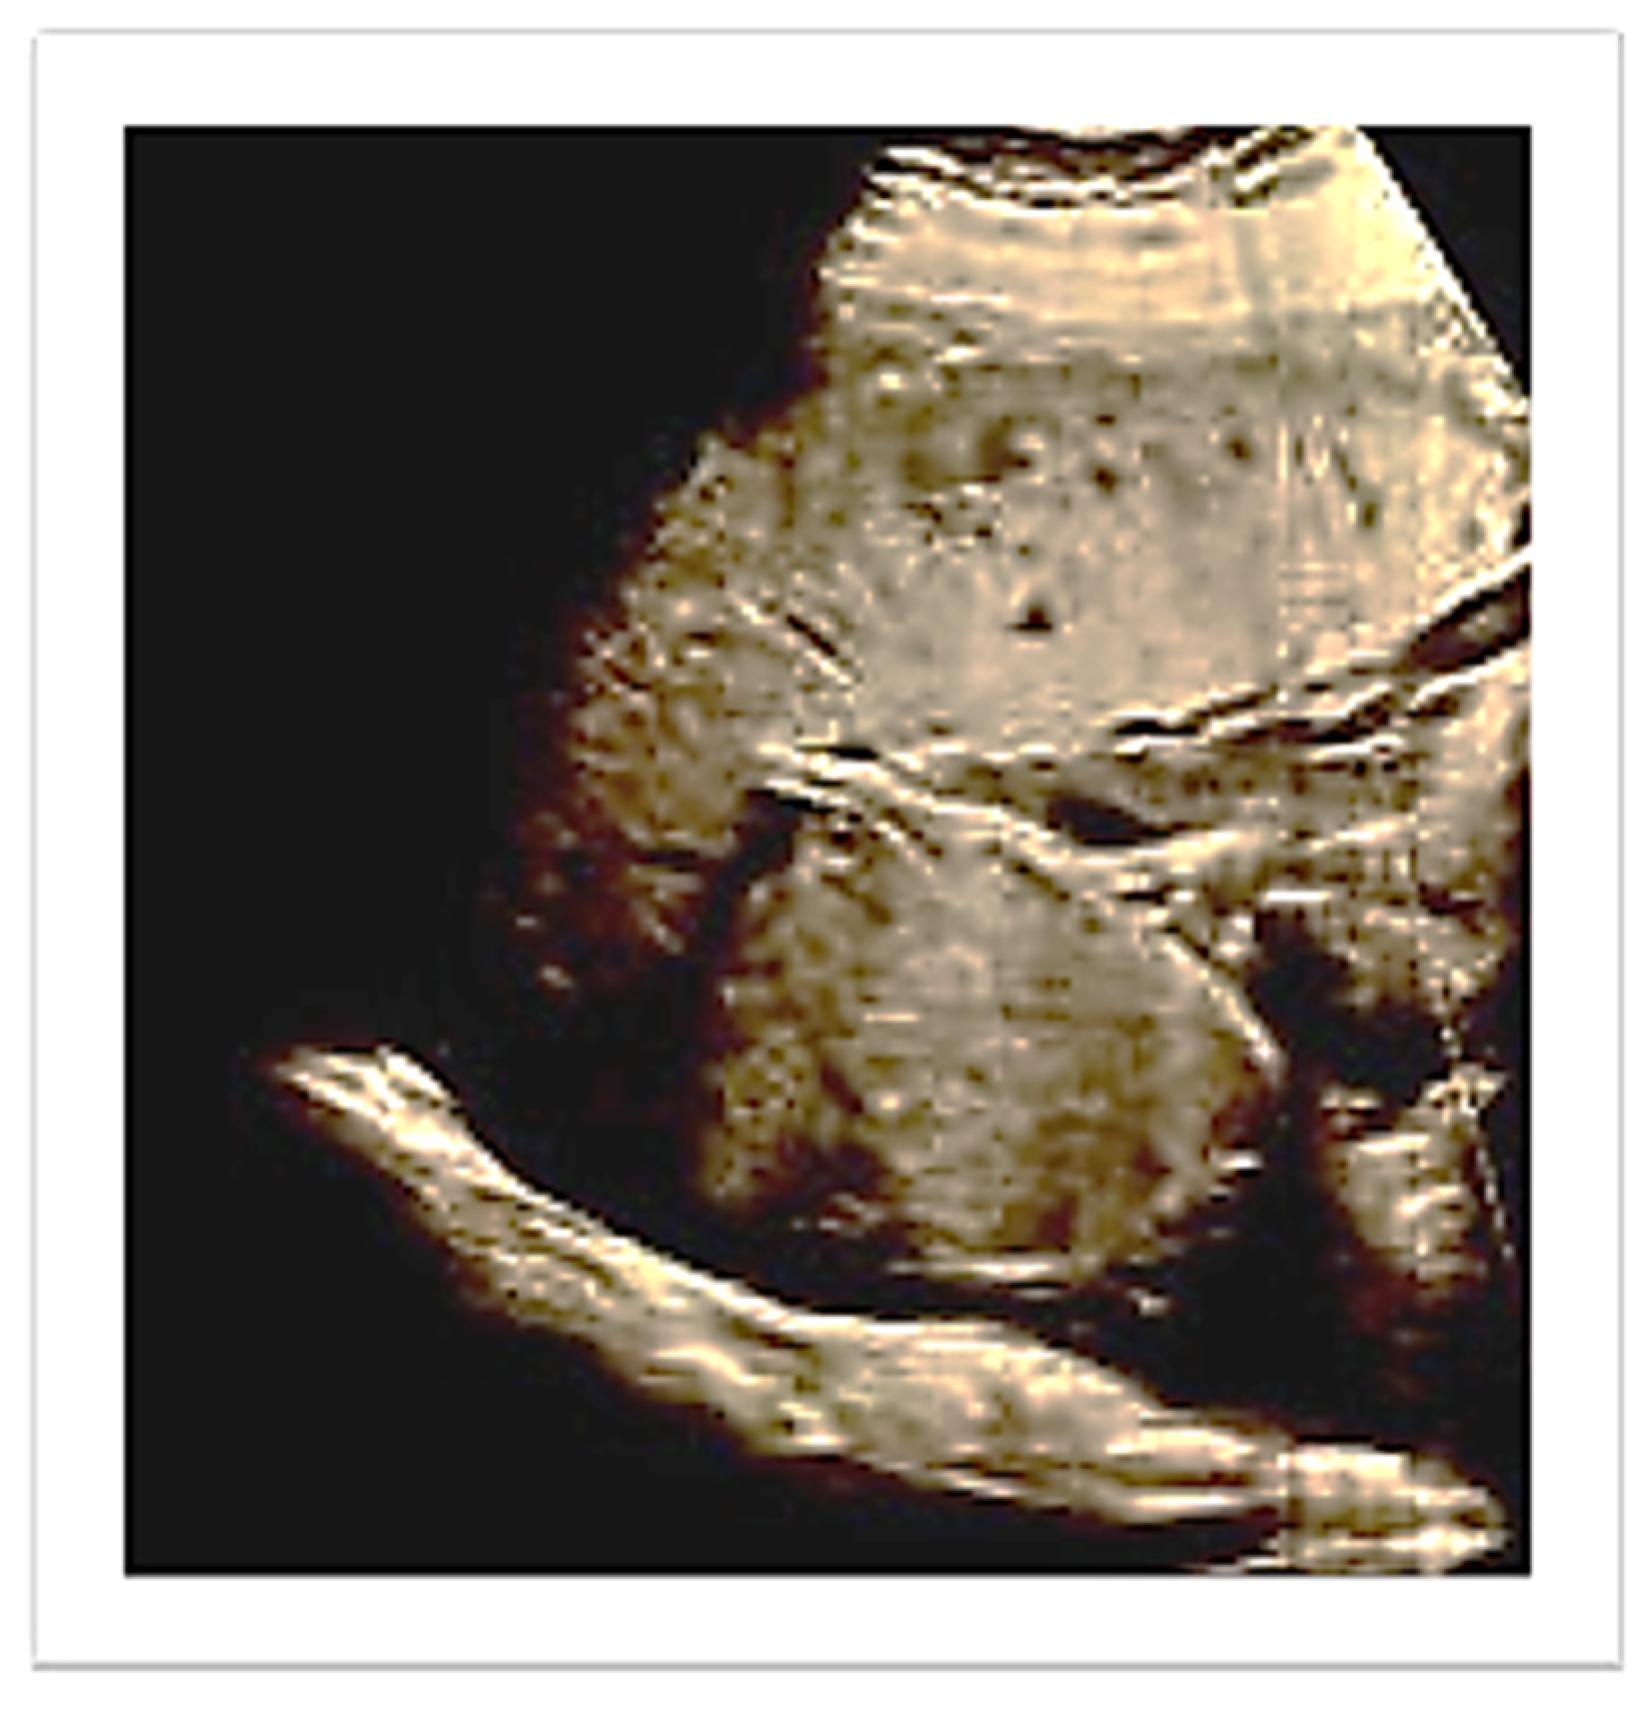

A vaginal delivery of a 2 kg male newborn occurred spontaneously after two days. The Apgar score at the 1st, 5th and 10th minute was, respectively, 10/10/10. Thirty minutes after delivery, despite active management of the third stage of labor, the placenta was still not delivered. An ultrasound evaluation showed the presence of an entangled placenta within the right uterine angle, and, according to Herman Ultrasound findings [12], the myometrium appeared thin at the placenta insertion but more than 2 mm (Figure 2), and there was no evidence of accreta spectrum.

Figure 2. Ultrasound evaluation of placenta location after birth. Number 1 demonstrates myometrial thickness measurement.